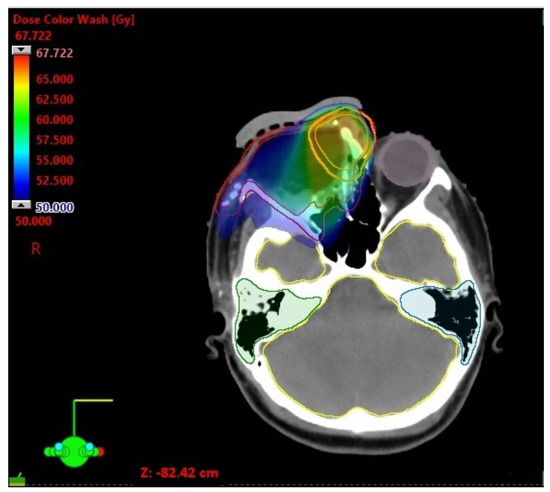

| D Min [Gy] | D Max [Gy] | D Mean [Gy] | |

|---|---|---|---|

| CTV 50 | 36.25 | 67.72 | 55.68 |

| PTV 50 | 6.76 | 67.72 | 54.12 |

| CTV 60 | 57.24 | 67.72 | 62.84 |

| PTV 60 | 39.32 | 67.72 | 62.02 |

| Brainstem | 17.94 | 35.28 | 25.15 |

| Optic chiasm | 20.48 | 35.26 | 26.61 |

| Cochlea left | 1.13 | 13.87 | 2.35 |

| Cochlea right | 28.73 | 42.43 | 34.94 |

| Lens left | 2.34 | 4.14 | 2.92 |

| Eye left | 1.52 | 34.52 | 4.55 |

| Brain | 0.27 | 60.12 | 9.20 |

| Optic nerve left | 4.54 | 32.74 | 16.24 |

| Parotid gland left | 0.70 | 4.39 | 2.44 |

| Parotid gland right | 3.64 | 49.51 | 28.09 |

| Spinal cord | 1.22 | 23.82 | 8.14 |

| Mandible | 0.28 | 48.86 | 10.20 |